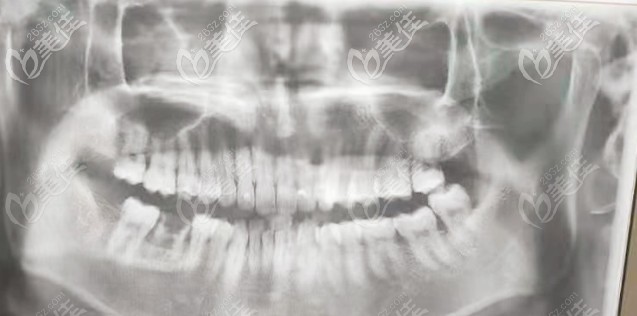

術(shù)前照片:

我的牙齒狀況:有一顆壞牙,需拔除后種植一顆新的牙齒。

我選擇的植體是瑞士ITI(又名士卓曼)種植體。